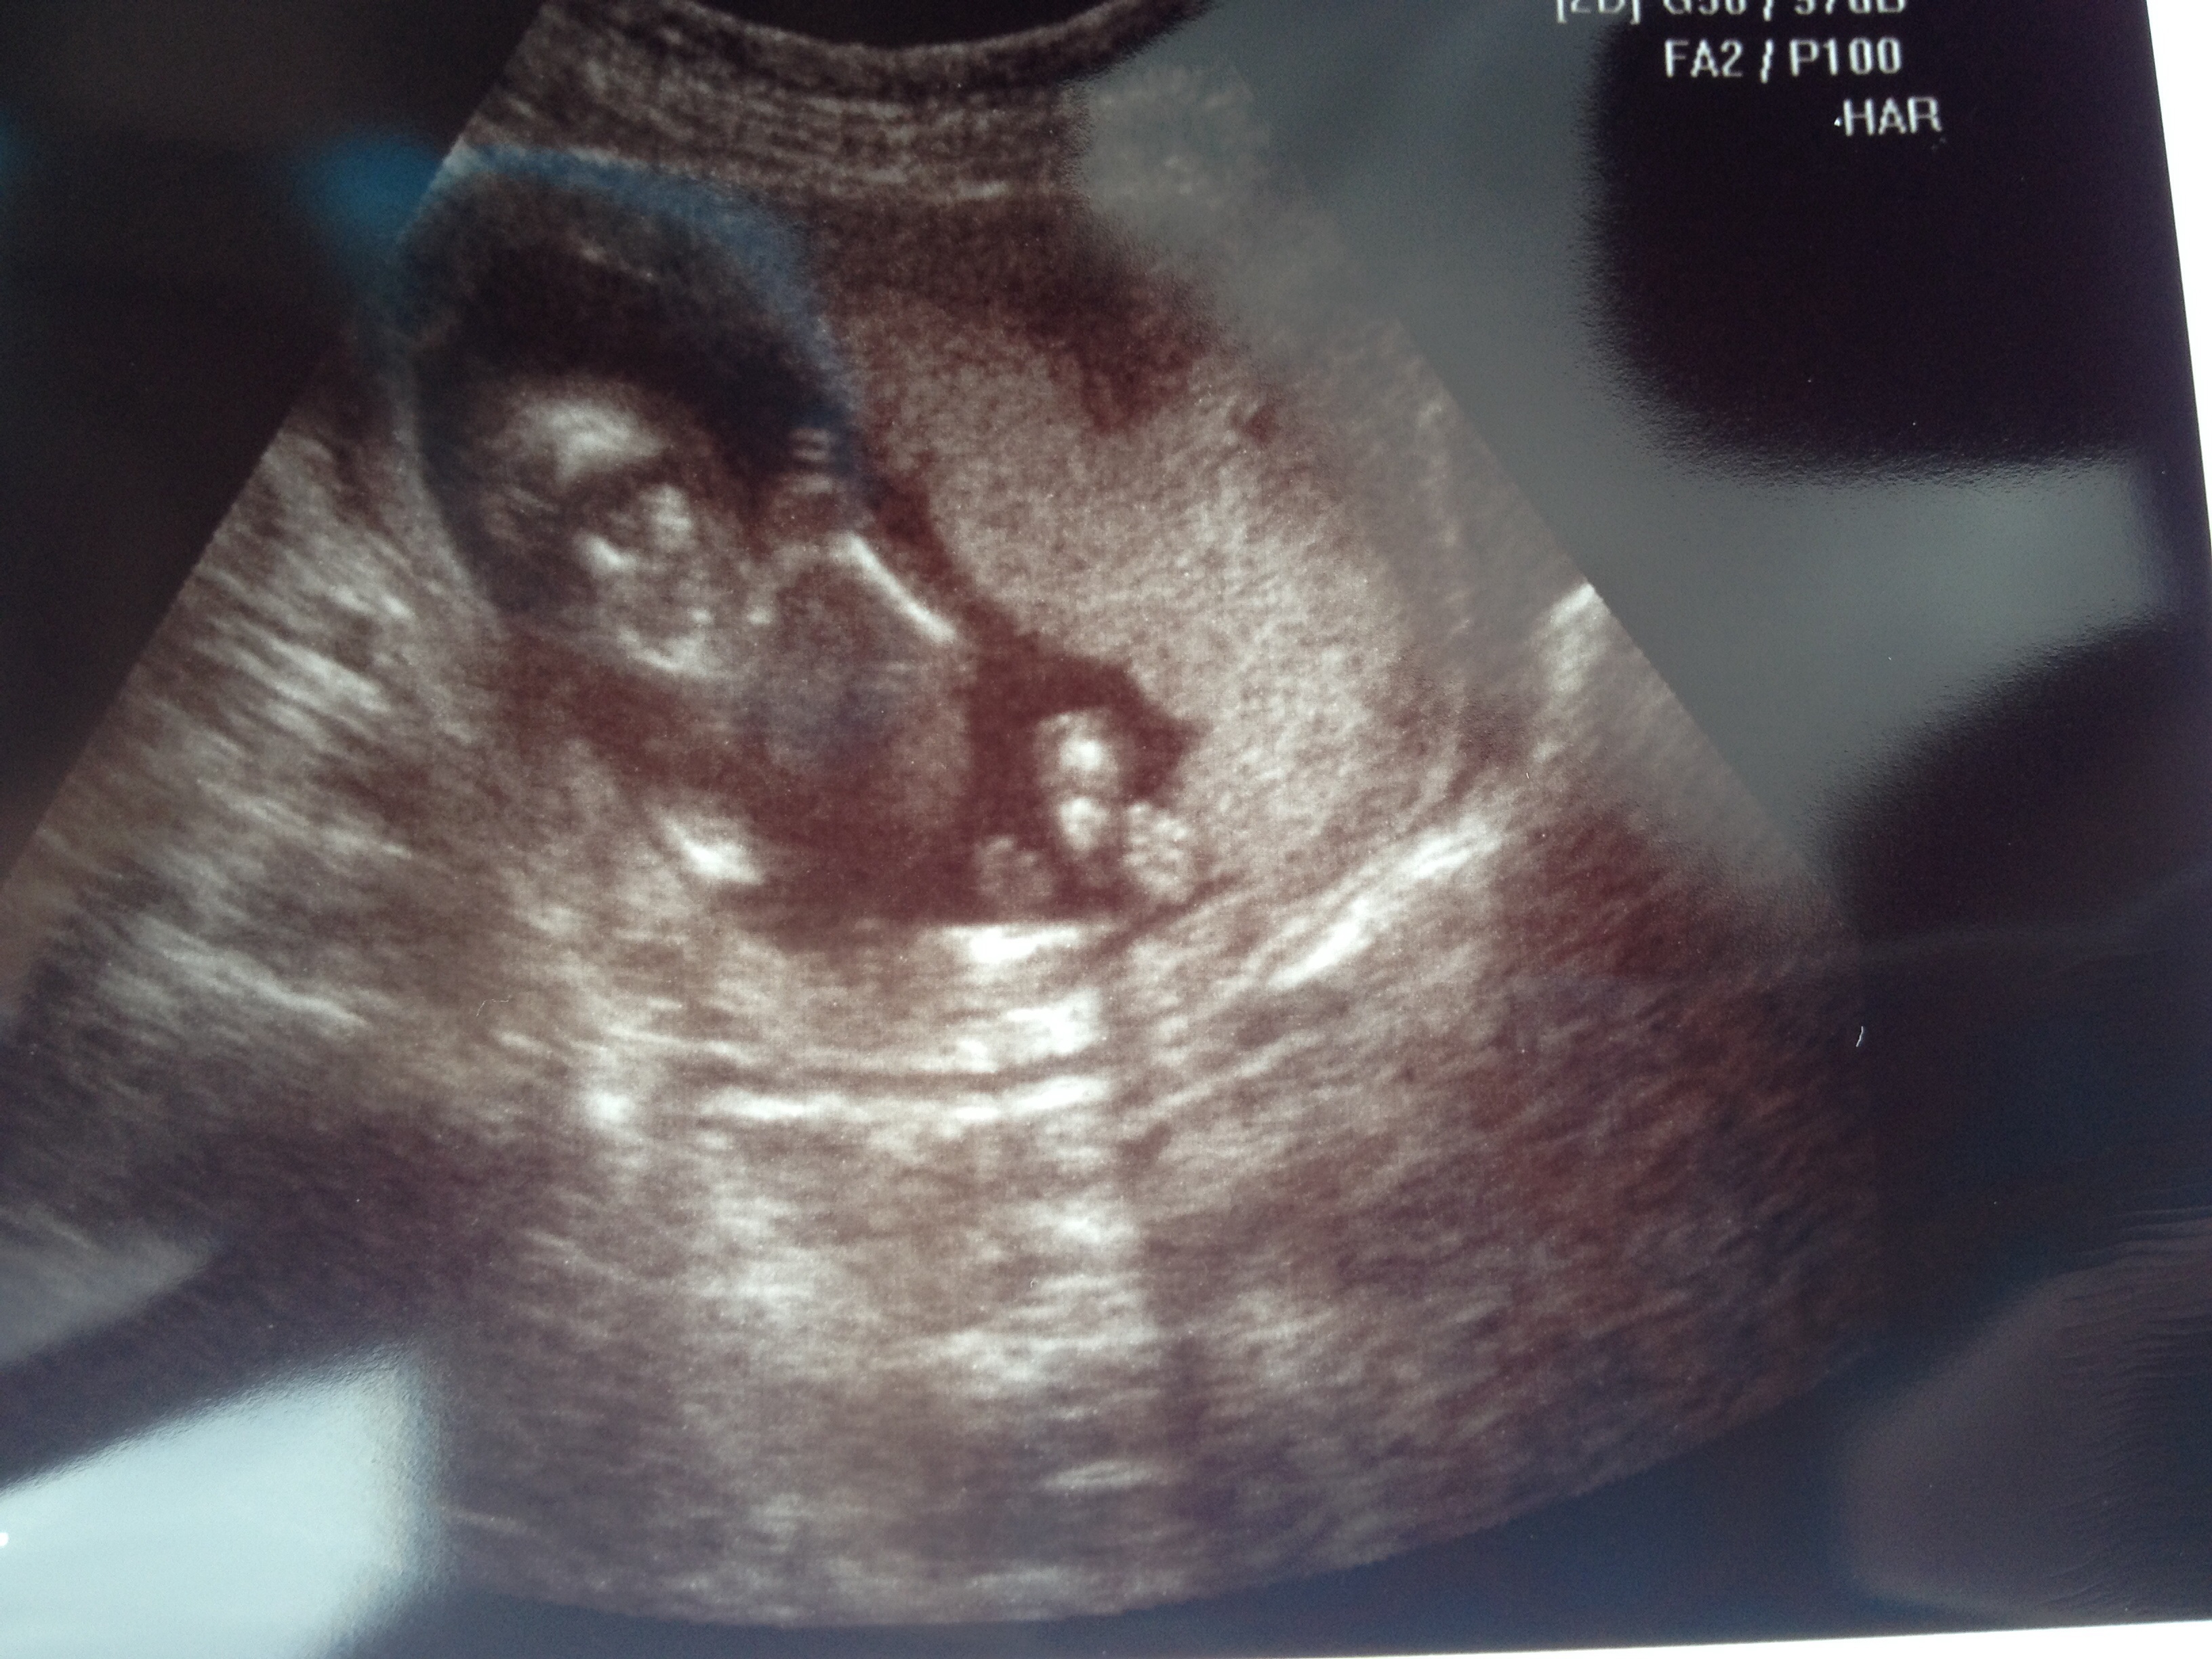

Update- LO looked awesome in the ultrasound, just chilling with his thumb in his mouth. Heart beat was great and everything looked perfect, so I am finally able to breathe. Thanks so much for all the support! It was so nice to hear during my big scare.

Oh, and the tech said baby is a boy, but I'm not sure I trust it since it's early. I'm just thrilled LO is okay!